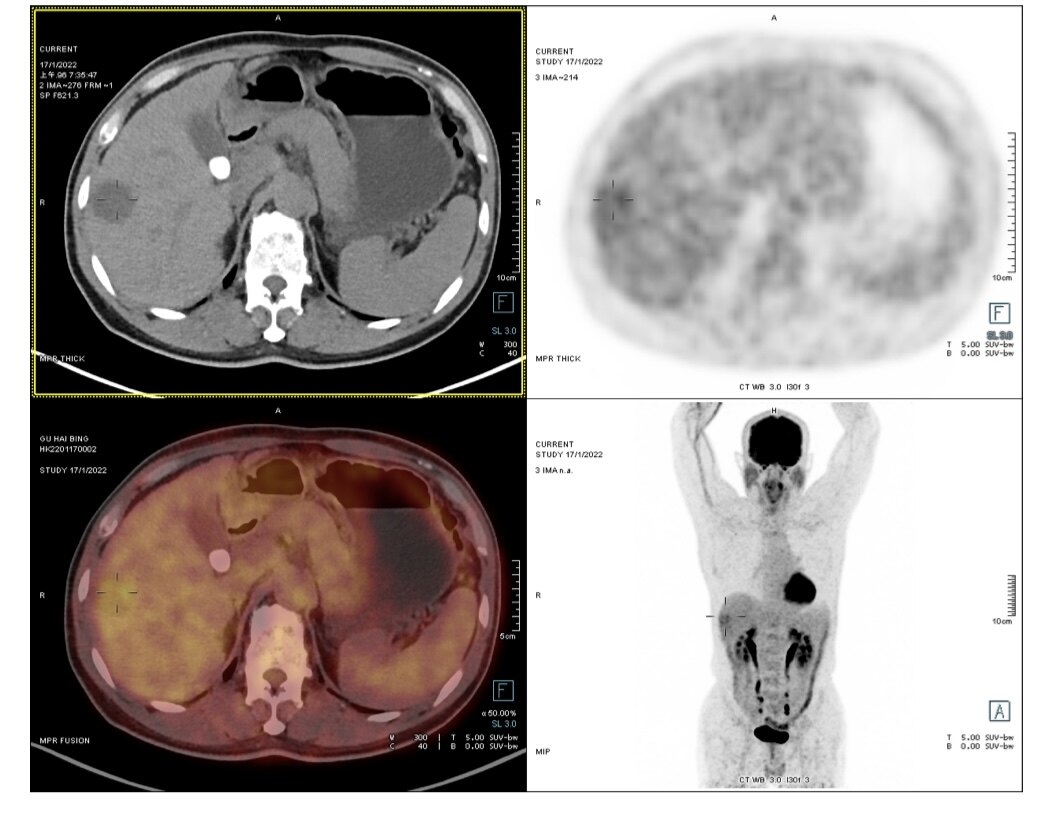

手术切除是早期肝癌安全(手术死亡率为0)、有效(5年生存率达到70%)、高性价比(报销前费用在3万元左右)的治疗方式。以下4例有乙肝病史,经定期筛查(肝脏B超和甲胎蛋白)发现的早期肝癌,手术切除后平均住院时间6天,无任何并发症,自费仅数千元。